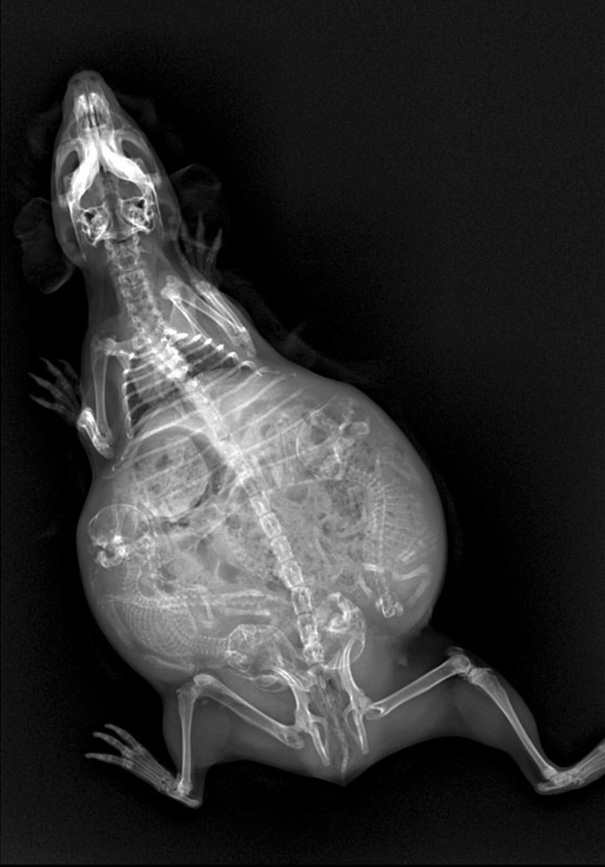

An X-Ray Of A Pregnant Guinea Pig?

A Pregnant Guinea Pig